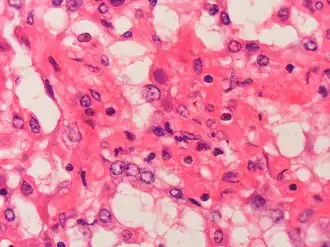

В организм инфекция попадает через слизистые оболочки верхних дыхательных путей, реже — кишечник либо конъюнктиву. Вирус попадает в эпителиальные клетки и клетки лимфоидной ткани, поражает цитоплазму и ядро, где происходит репликация вирусной ДНК. Поражённые клетки прекращают деление и погибают. Вирусы проникают в другие клетки слизистых оболочек и лимфатических узлов, а также в кровь. Это сопровождается массивным экссудативным воспалением со стороны слизистых, т.е. накоплением в них жидкости. Появляется конъюнктивит. Далее в патологический процесс вовлекаются внутренние органы (лёгкие, бронхи, кишечник, почки, печень, селезёнка), а также головной мозг, мезентериальные лимфоузлы.[3]